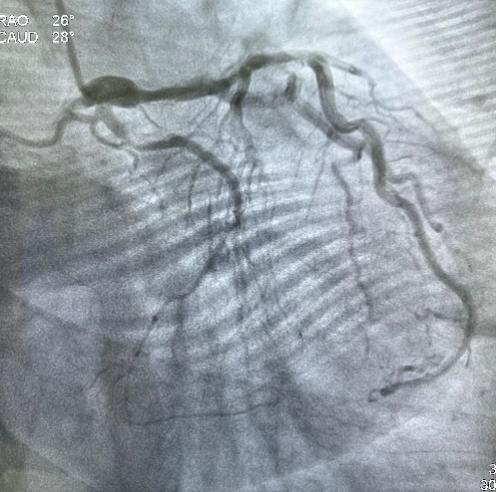

3月8日经过充分的术前准备,雷新军教授带领景林德博士和蔡安琪医生按照预定方案为患者实施了手术。冠脉造影示:RCA 2段慢性闭塞合并重度钙化,闭塞段长约30 mm,同向桥侧支供血使其远段显影(图3a);前降支散在斑块伴钙化,狭窄约25%-50%,并通过间隔支侧支循环向右冠逆向供血(图3b);回旋支11段狭窄约75%(图3c)。决定干预右冠:指引导管到位后在Guidezilla的支撑下,经Corsair微导管仔细操控GAIA 3rd穿过闭塞段进入远端血管真腔(图3d,e);然后通过微导管交换成旋磨导丝,使用1.5 mm Burr进行冠脉内斑块旋磨并抛光(图3f),造影见右冠恢复TIMI 3级前向血流,但2段残余狭窄最重处仍达90%(图3g);遂经导丝送入3.0*12 mm“Shockwave”冲击波球囊分段进行血管内碎石术:首先将压力充盈至4 atm后开始释放脉冲,松解钙化斑块,然后再将充盈压升至6 atm维持10秒,对靶病变进行低压球囊扩张成形(图3h);再次造影见右冠2段局限性夹层,闭塞段残余狭窄<10%(图3i),效果非常满意,遂由远及近衔接植入BioFreedom支架(图3j),历时约1小时手术成功,病人安返病房。

图3 经皮冠脉介入治疗